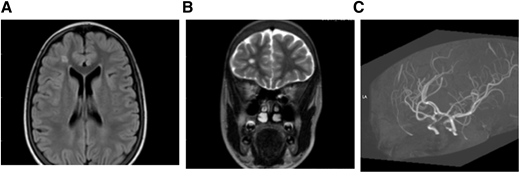

MRI (A) FLAIR (axial) and (B) T2W (coronal). Brain images from a 15-year-old female with SCA without neurologic complications according to history from parents and child. SCI seen in 2 planes measuring .3 mm in right frontal lobe deep white matter. (C) MRA: right and left cavernous ICA stenosis.